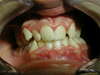

Nos Cas Cliniques orthodontiques 2

Photos avant traitement